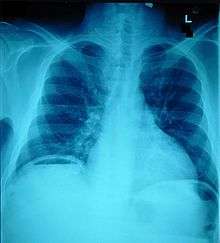

Abdominal trauma is an injury to the abdomen. It may be blunt or penetrating and may involve damage to the abdominal organs.[1] Signs and symptoms include abdominal pain, tenderness, rigidity, and bruising of the external abdomen. Abdominal trauma presents a risk of severe blood loss and infection. Diagnosis may involve ultrasonography, computed tomography, and peritoneal lavage, and treatment may involve surgery.[2] Injury to the lower chest may cause splenic or liver injuries.[3]